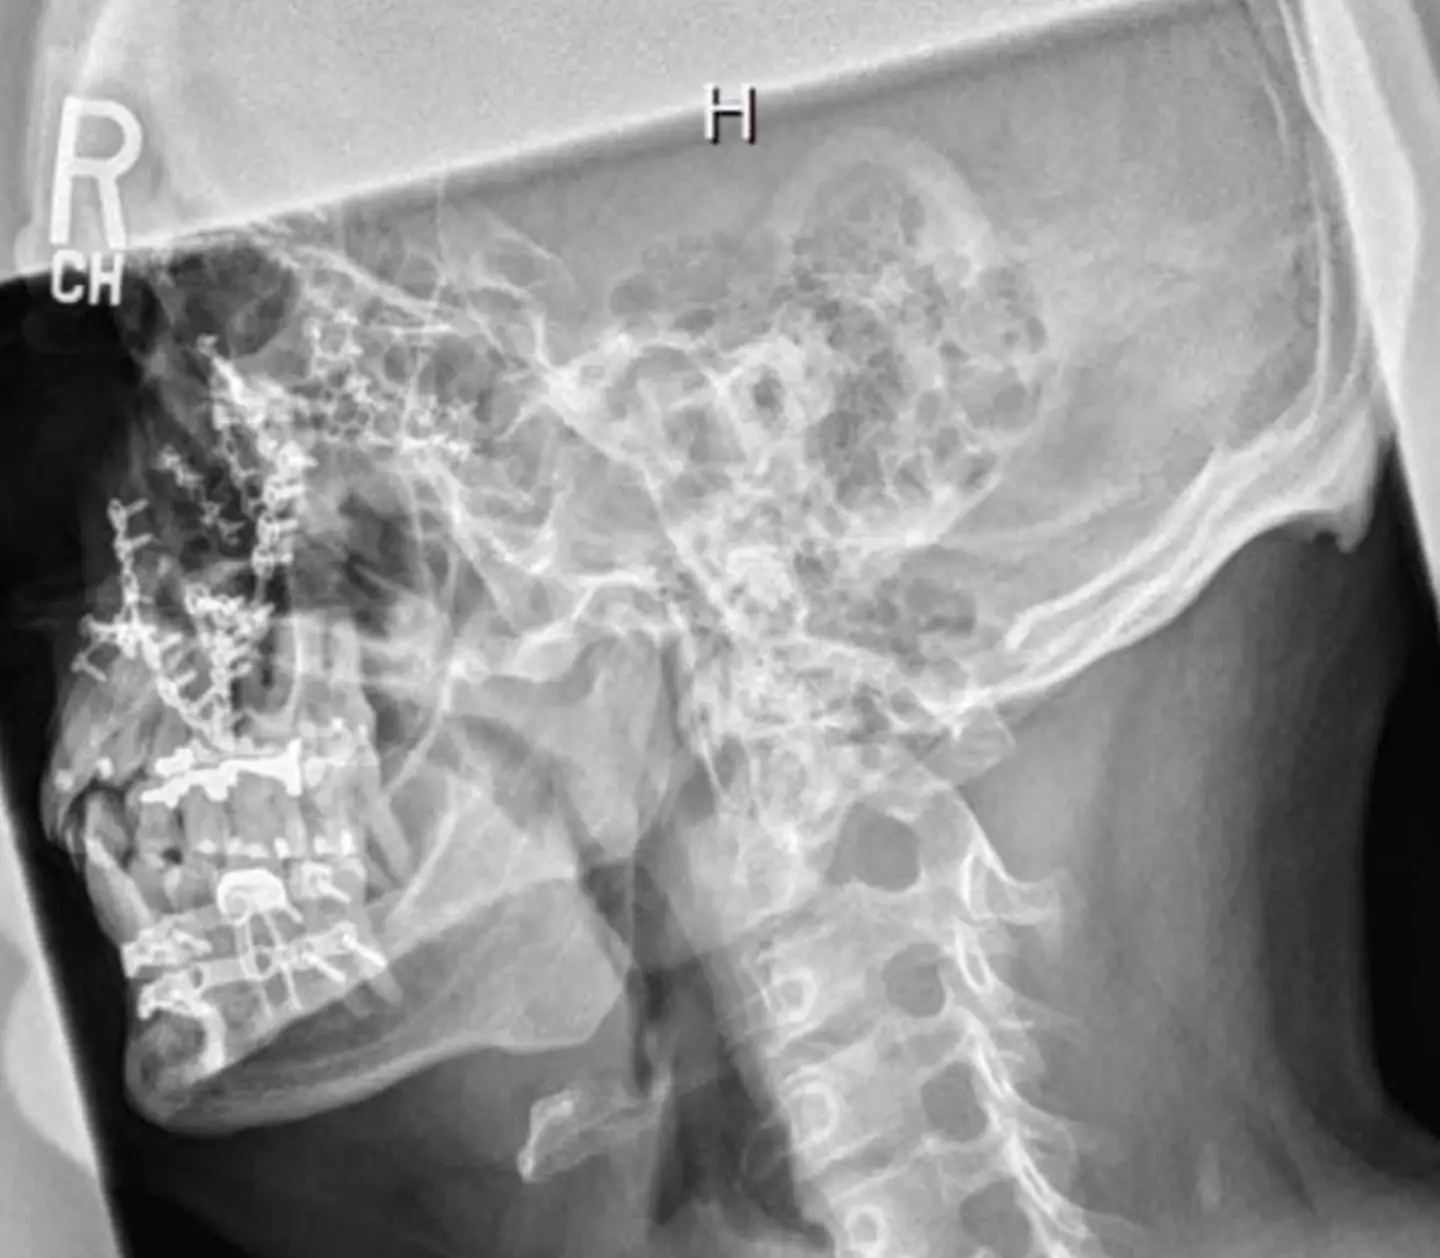

Over time, Mike's face was reconstructed with the help of 110 screws and 20 titanium plates.